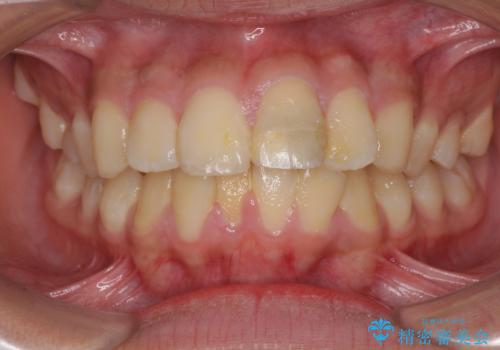

- 口元の突出感を気にして来院された患者様です。

上下前歯が著しく前突している状態であったので、上下左右の第1小臼歯4本を抜歯し、ワイヤー装置にて矯正治療を行うこととしました。

舌の突出癖により、前突になったと考えられたため、舌のトレーニングをしっかりと行うよう指導しました。